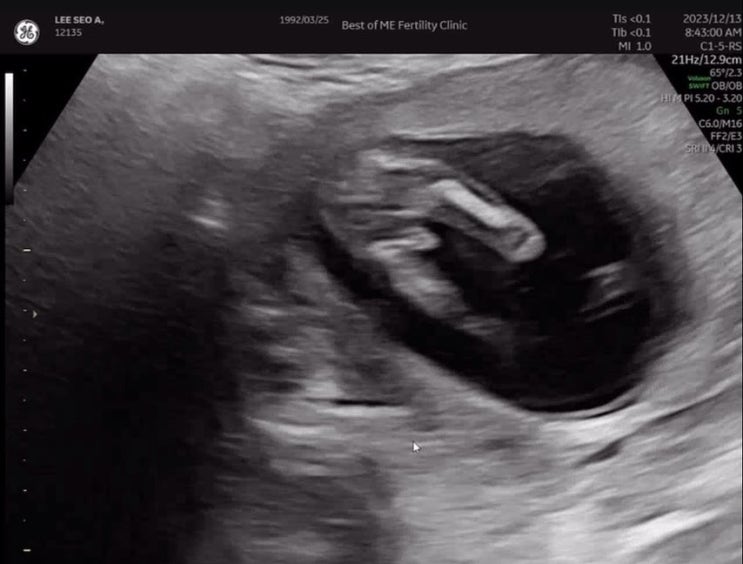

임신일기/베스트오브미여성의원 난임졸업! 모두 친절해서 좋았던곳

임신 15주차 이제 난임병원을 졸업했다 ! 처음 지인 소개로갔던 베스트오브미여성의원 구화선원장님 소개받...

임신일기/임신14주차 성별확인/서울시 임산부혜택 엄마북돋움 신청하고 무료로 아기책받아요

임신 14주차에 아기 성별확정받을줄 몰랐네,,,ㅎㅎ 너무 빼박이라 변함 없는지 원장님도 보시자마자 변함없...